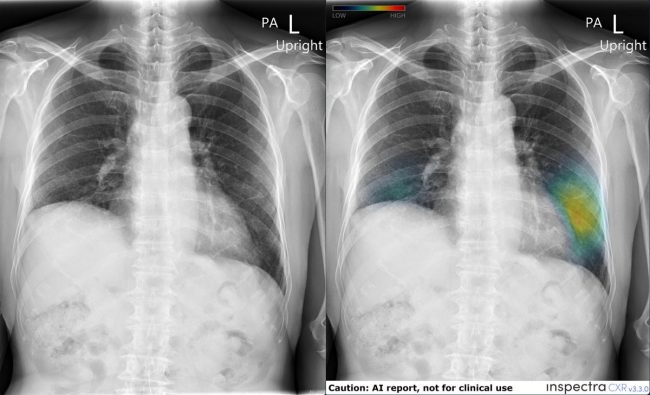

ซึ่งการนำระบบ AI มาใช้ เสมือนเป็นผู้ช่วยรังสีแพทย์ เพื่อให้อ่านผลได้อย่างความถูกต้อง แม่นยำ ทำให้ความผิดพลาดน้อยลง และยังสามารถช่วยจัดลำดับความเร่งด่วนในการอ่านผลสำหรับคนไข้ที่มีผลผิดปกติเร่งด่วน ทำให้คนไข้จะได้รับการรักษาที่ทันท่วงที Inspectra CXR สามารถบอกความผิดปกติได้ครอบคลุม รอยโรคที่สำคัญหลายอย่างในภาพเอกซเรย์ปอด การใช้งานง่าย ไม่เพิ่มภาระในการทำงานให้กับรังสีแพทย์

สุพิชญา พู่พิสุทธิ์ ประธานเจ้าหน้าที่บริหาร บริษัท เพอเซ็ปทรา จำกัด กล่าวว่า เทคโนโลยีปัญญาประดิษฐ์เป็นเทคโนโลยีที่ค่อนข้างใหม่ในประเทศ แต่ปัจจุบันทั่วโลกให้การยอมรับสำหรับการนำไปใช้งานและสามารถช่วยแพทย์ได้จริง โรงพยาบาลกรุงเทพเล็งเห็นถึงความสำคัญและมีวิสัยทัศน์ในการนำเทคโนโลยีมาประยุกต์ใช้ เพื่อยกระดับการให้บริการผู้ป่วยให้ดีขึ้นอย่างสม่ำเสมอ ไม่ว่าจะเป็นการนำระบบปัญญาปะดิษฐ์มาใช้เป็นเพื่อนคู่คิดของแพทย์รังสี ช่วยเตือนตำแหน่งรอยโรคที่บางครั้งอาจยากที่จะเห็นได้ด้วยสายตามนุษย์ หรือการนำเทคโนโลยีมาทำให้ระบบการทำงานของแพทย์มีประสิทธิภาพดียิ่งขึ้นและให้บริการผู้ป่วยได้เพิ่มมากขึ้นอีกด้วยระบบ Inspectra CXR เป็นซอฟต์แวร์ปัญญาประดิษฐ์ที่พัฒนาขึ้นเพื่อเพิ่มประสิทธิภาพในการทำงานของแพทย์ โดย AI ถูกเทรนให้มีความไวสูงในการตรวจจับรอยโรคบนภาพถ่ายเอกซเรย์ทรวงอก สามารถบ่งชี้ตำแหน่งที่ผิดปกติ รอยโรคที่อาจมีขนาดเล็ก หรือรอยโรคที่ทับซ้อนกับอวัยวะอื่นได้ โดยระบบ AI จะทำงานร่วมกับแพทย์เพื่อช่วยให้แพทย์ตัดสินใจได้เร็วขึ้นและผิดพลาดน้อยลง ระบบ Inspectra CXR เป็น AI มีประสิทธิภาพเทียบเคียงกับ AI ที่ดีที่สุดในเวทีโลก และถูกเทรนจากภาพถ่ายเอกซเรย์คุณภาพสูงจากกว่า 1.5 ล้านภาพทั่วโลก โดยเป็นภาพถ่ายของคนไทยมากกว่า 40% ทางบริษัทนำเอาอัลกอริทึมความแม่นยำสูงที่สามารถตรวจจับครอบคลุมทุกรอยโรคมาผนวกกับเทคโนโลยีอื่นที่ตอบโจทย์โรงพยาบาลเช่น ระบบรักษาความปลอดภัยของข้อมูลที่เข้มแข็ง และระบบจัดการข้อมูลที่ทันสมัย ทั้งหมดนี้ทำให้ Inspectra CXR เป็นแพลตฟอร์มที่สร้างมาตรฐานใหม่ในการวินิจฉัยภาพถ่ายทางการแพทย์ได้